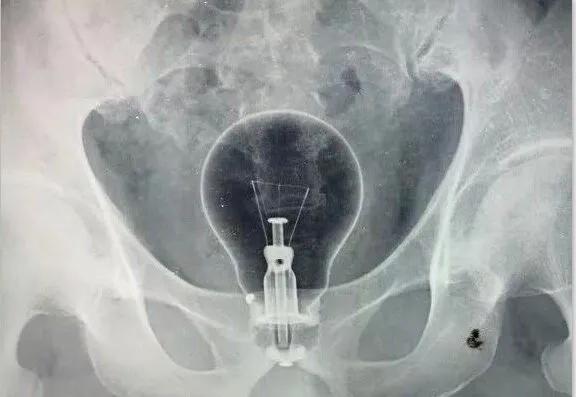

正如上所说,肛肠科之所以能够在每家医院成为传奇那是有它独特之处的,因为医院大部分劲爆的新闻都出自肛肠科。上次我们所讲的“菊花掏玻璃瓶”只是管中窥豹而已,各种稀奇古怪的作品都能进去菊花,吃的、用的、看的,能动的、不能动的,没有最劲爆只有更劲爆!

放错位置的灯泡